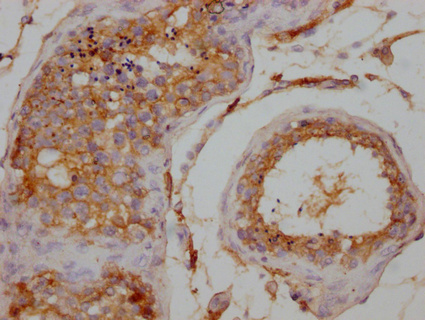

• IHC image of CSB-PA026120LA01HU diluted at 1:200 and staining in paraffin-embedded human testis tissue performed on a Leica BondTM system. After dewaxing and hydration, antigen retrieval was mediated by high pressure in a citrate buffer (pH 6.0). Section was blocked with 10% normal goat serum 30min at RT. Then primary antibody (1% BSA) was incubated at 4°C overnight. The primary is detected by a Goat anti-rabbit IgG labeled by HRP and visualized using 0.05% DAB.